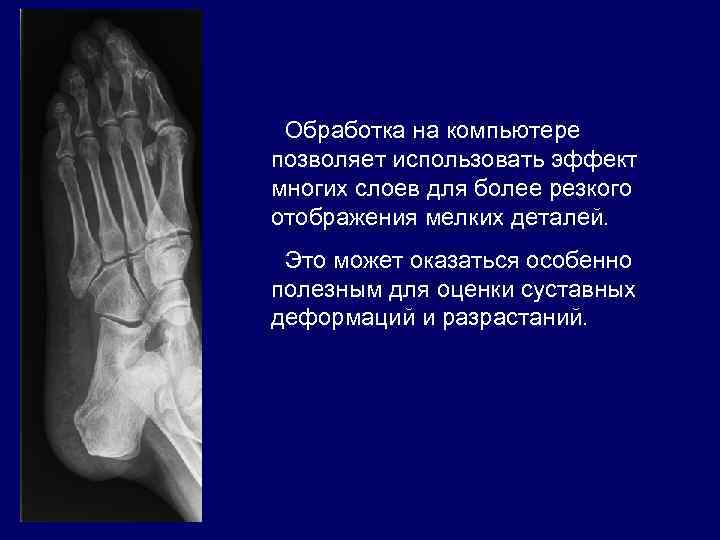

Обработка на компьютере позволяет использовать эффект многих слоев для более резкого отображения мелких деталей. Это может оказаться особенно полезным для оценки суставных деформаций и разрастаний.